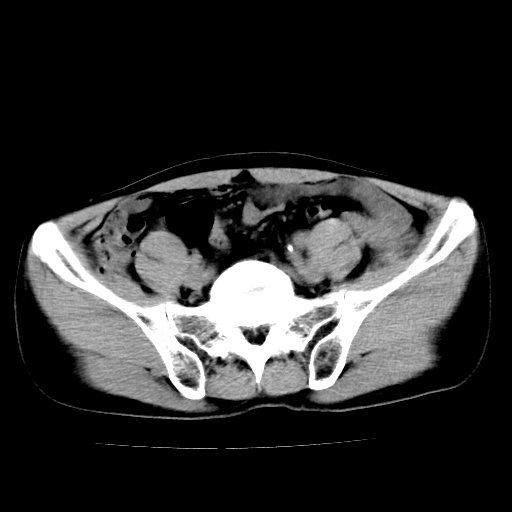

男,47岁,左输尿管结石碎石治疗后10余日。彩超示:左输尿管下段狭窄、输尿管积水。请各位讨论一下左输尿管下段结石还是静脉石?

象是第二狭窄处结石伴以上输尿管、肾盂轻度积水。

输尿管结石伴以上输尿管、肾盂轻度积水。

两侧髂总动脉壁斑状及点状钙化.左侧输尿管行经与左髂总动脉相交后见高密度影,且下段输尿管管腔未见扩张,应该要考虑结石伴以上输尿管及肾盂积水.但右侧结节状高密度影,也应该是结石吧!那以上输尿管未见扩张呢!因此静脉结石可能性也较大.请问楼主碎石前左侧输尿管结石位置.

虽左侧有轻度肾盂积水但不支持结石。1结石边周应该有软组织包绕呈晕征。2钙化点前面见输尿管影也不支持是结石。3彩超没提结石。建议超生复查。

输尿管先位于腹部,后进入盆腔,最后斜穿膀胱壁开口于膀胱,因此,临床上常将输尿管分为腹段、盆段和壁内段。第1个狭窄:在肾盂与输尿管移行处。第2个狭窄:在跨过髂血管处。第3个狭窄:在穿过膀胱壁处。这些狭窄是结石容易滞留的部位。

左侧输尿管有轻度扩张伴有肾盂积水,输尿管下段周围的高密度影不象在输尿管内。

同意,不支持结石。(因显示该高密度影前见扩张输尿管影,另外两侧对称显示)。

左侧高密度影在左侧输尿管的内侧方,所以不考虑输尿管结石.

我认为不是结石的可能性大,因为他的位置和血管钙化的位置邻近